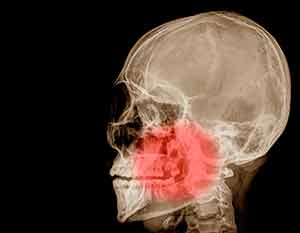

Лечение сустава нижней челюсти

Сегодня подобная проблема возникает у очень многих людей, причем зачастую независимо от возраста человека. Если челюсть щелкает и болит, если Вы чувствуете что сустав начинает хрустеть, то знайте, источником этого явления обычно становится дисфункция височно-нижнечелюстного сустава (ВНЧС). Боль, отдающая в височную область, хруст при движениях челюстью, а также жевании – комплексный симптом именно такого заболевания.

Почему возникает и как проявляется дисфункция ВНЧС?